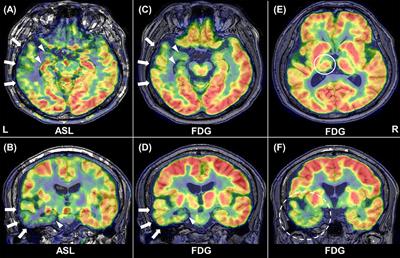

Case Report

Published on 06 Jan 2025

in Neuro-Oncology and Neurosurgical Oncology